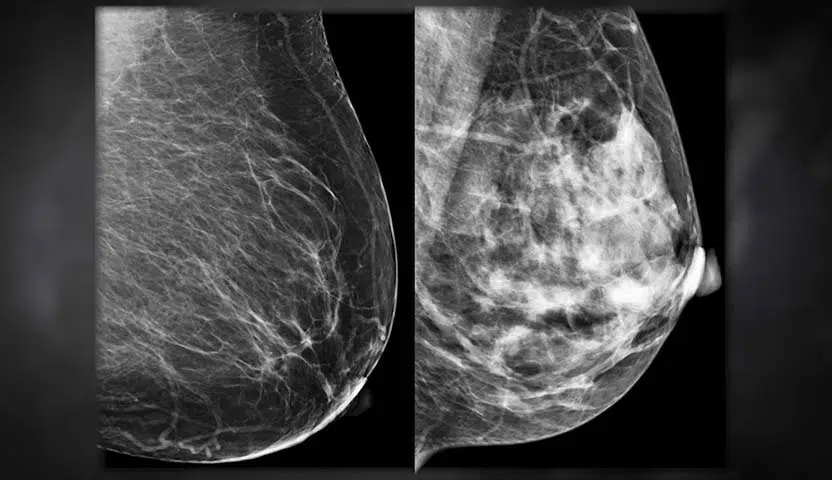

شكل سرطان الثدي في الأشعة

شكل سرطان الثدي في الأشعة السينية

تظهر صور الثدي الناتجة عن جهاز الماموجرام باللونين الأبيض والأسود، وعادًة ما تكون الصور رقمية تظهر على شاشة الكمبيوتر، ويكون تفسيرها متعلق بالأسنجة، فمثلا الأنسجة الكثيفة في الجسم مثل العظام تظهر باللون الأبيض على الأشعة السينية، بينما تظهر الدهون باللون الرمادي الداكن على الأشعة السينية.

شكل سرطان الثدي في الأشعة السينية وبعض حالات الأورام الحميدة تكون أكثر كثافة من الدهون، وتظهر بدرجة أفتح من اللون الرمادي وأغمق من الأبيض.

هذه التفسيرات يتم توضيحها بواسطة طبيب أشعة مختص، حيث يقوم الطبيب بترجمة الصور الخاصة بكل حالة في صورة تقرير طبي يوضح الحالة الصحية الخاصة بالمريضة.

في النهاية، شكل سرطان الثدي في الأشعة يكون مميز بطريقة كبيرة، ويمكن تمييزه من قِبل طبيب الأشعة المختص الذي يقوم بتحليل الصور التي يحصل عليها من الفحص، ويقوم بترجمتها إلى تقرير يستطيع طبيب الأورام فهمه، وتحضير خطة العلاج المناسبة للمريضة بناءًا عليه.